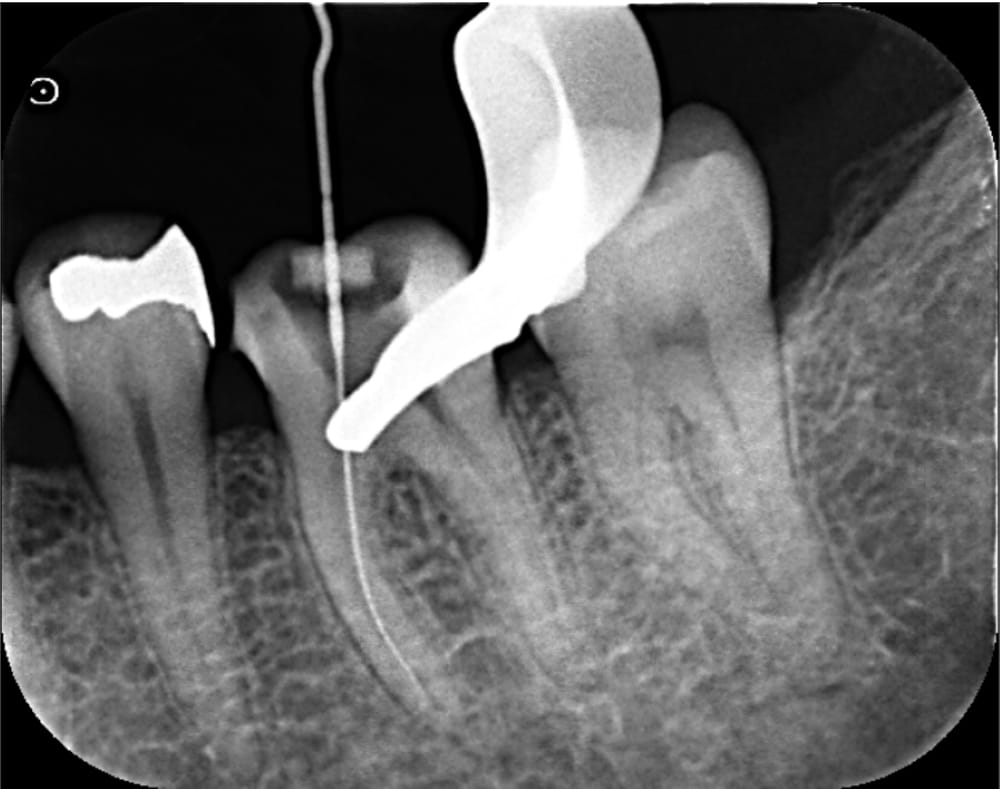

2回目の来院時には、当初抱えていた強い痛みはかなり軽減していました。

根管内を徹底的に清掃し、充填のためのガッタパーチャポイントを試適し、根管充填+コア築造まで完了しました。